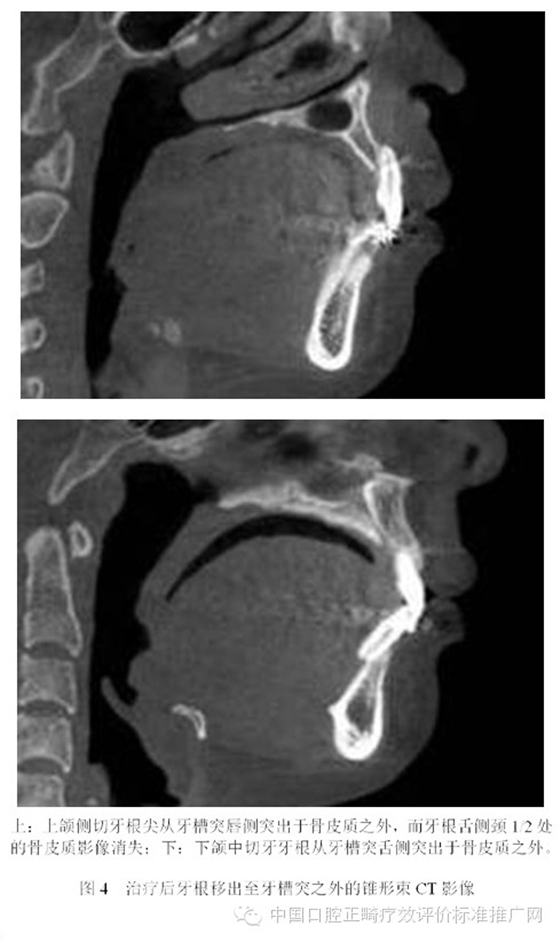

為了避免支抗的丟失,正畸醫(yī)師終于發(fā)現(xiàn)了最強(qiáng)的支抗裝置---金屬種植釘支抗。在用支抗磨牙拉前突的切牙時,切牙牙根在接觸腭側(cè)骨皮質(zhì)后移動的阻力會非常大,于是支抗磨牙會前移而最終關(guān)閉間隙;但當(dāng)改用種植釘支抗拉前牙時,由于種植釘是絕對支抗,在矯治力作用下幾乎不動[6],因此當(dāng)切牙牙根與腭側(cè)骨皮質(zhì)接觸后,種植釘仍然不會作任何讓步,那么進(jìn)一步對抗的結(jié)果會怎么樣?理想的結(jié)果是腭側(cè)骨皮質(zhì)的牙根一側(cè)發(fā)生骨吸收,而舌側(cè)骨板發(fā)生骨沉積,牙齒帶著牙槽骨一起向腭側(cè)移動。問題是骨吸收與骨沉積的數(shù)量相等嗎?速度一致嗎?為了回答這個問題,筆者[7]10年前作過一個上頜切牙內(nèi)收對其前后方牙槽骨改建的探索性研究。該研究選擇55例平均年齡為13.3歲的青少年錯合患者為研究對象,采用拔除上下頜第一前磨牙進(jìn)行矯治,平均保持時間為3年。通過測量上切牙阻力中心前方及后方牙槽骨在治療前、治療后及保持后的骨量變化,以及牙槽突總厚度在上述3個時間點的變化,結(jié)果發(fā)現(xiàn):上切牙阻力中心在治療后向腭側(cè)平均移動了1.8mm (P<0.001);與阻力中心水平的唇側(cè)牙槽骨厚度增加了0.2mm (P<0.01),腭側(cè)牙槽骨厚度減小了0.8mm (P<0.001);隨訪期上切牙阻力中心向唇向復(fù)發(fā)了0.8mm (P<0.01),與阻力中心水平的唇側(cè)牙槽骨厚度相應(yīng)減小了0.2mm (P<0.05),但腭側(cè)牙槽骨厚度卻并沒有明顯的增加;與上切牙阻力中心水平的牙槽突總厚度基本保持在治療后的水平。由此可見,在牙齒移動的過程中,牙槽骨的生物學(xué)改建是以骨吸收為主,骨增生十分有限,即使是保持3年以后,骨增生的量也未達(dá)到其吸收的量。雖然這只是個初淺的臨床研究,尚有待基礎(chǔ)研究去證實,但它卻部分解釋了正畸臨床上在對骨性錯合患者進(jìn)行牙代償性矯治時,會出現(xiàn)牙槽骨吸收、裂隙、穿孔,牙齦萎縮或部分根尖移出牙槽骨的現(xiàn)象[8-13]。圖3為1例成人患者在用牙代償性治療方法減少重度深覆蓋深覆合時出現(xiàn)切牙根尖從舌側(cè)移出牙槽骨的X線影像;圖4為1例采用種植釘支抗大量內(nèi)收上下頜前牙的患者,治療后牙根移出至牙槽突之外的錐形束CT影像。